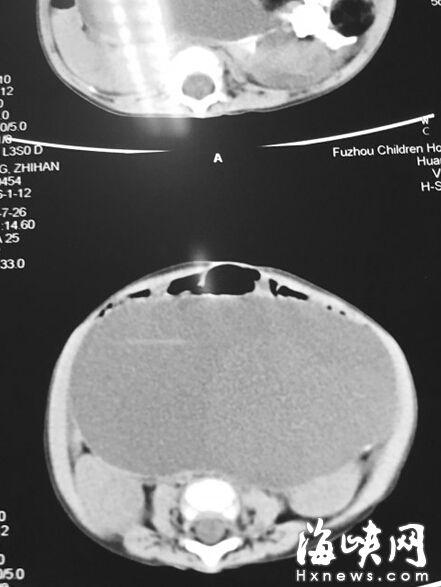

CT顯示,小云腹腔被畸胎瘤霸占

7月22日,家人抱著小云到福州兒童醫(yī)院,福州兒童醫(yī)院副院長、小兒外科學博士林芃一摸她肚子,推斷可能是巨結(jié)腸或腫瘤。果然,B超結(jié)果顯示,小云 的左側(cè)腹膜后藏著一個巨大腫瘤,被腸管擋住了,為此多次漏診。腫瘤直徑約20厘米,幾乎霸占整個腹腔。7月29日,醫(yī)生花了3個小時剝離腫瘤,其皮質(zhì)硬。 醫(yī)生將瘤中的液體吸出500多毫升,“排球”癟了1/3,才被順利取出。這是一個畸胎瘤,足有2斤重,這么大的很罕見。但畸胎瘤分化不成熟,沒有成形的毛 發(fā)、牙齒等組織,很可能是惡性腫瘤,目前還在等病理報告。